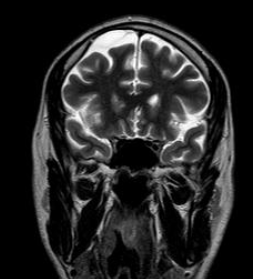

Медицинские аспекты и диагностика субдуральной гигромы мозга